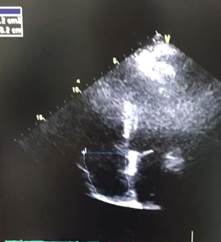

A las 48 horas de ingreso en UCI presenta de forma súbita deterioro hemodinámico e hipoxemia refractaria que no mejoraba, a pesar de encontrase en decúbito prono y con parámetros ventilatorias adecuados. Se procedió a realizar ecocardiograma (Fig. 1) que reporta ventrículo izquierdo con  diámetros conservados, motilidad conservada, función sistólica FEVI 61% por Simpson, cavidades derechas dilatadas VD 4.2 basal,  TAPSE 1 cm, onda S 0.07 m/seg, vena cava 1.7 cm, en el eco doppler llenado diastólico con patrón normal, insuficiencia tricuspidea moderada Vmax 3.2 m/seg, PSP aproximada 45 mmhg, disfunción sistólica del VD, dilatación de cavidades derechas.

Figura 1. Ecocardiograma previo a tratamiento fibrinolítico. A Disfunción sistólica de VD con TAPSE 1, B Insuficiencia tricúspidea con Vmax 3,2 m/seg , C Dilatación de cavidades derechas

Figura 3. Ecocardiograma Post-fibrinólisis. A función sistólica de VD adecuada TAPSE 1,9. B Cavidades derechas normales.